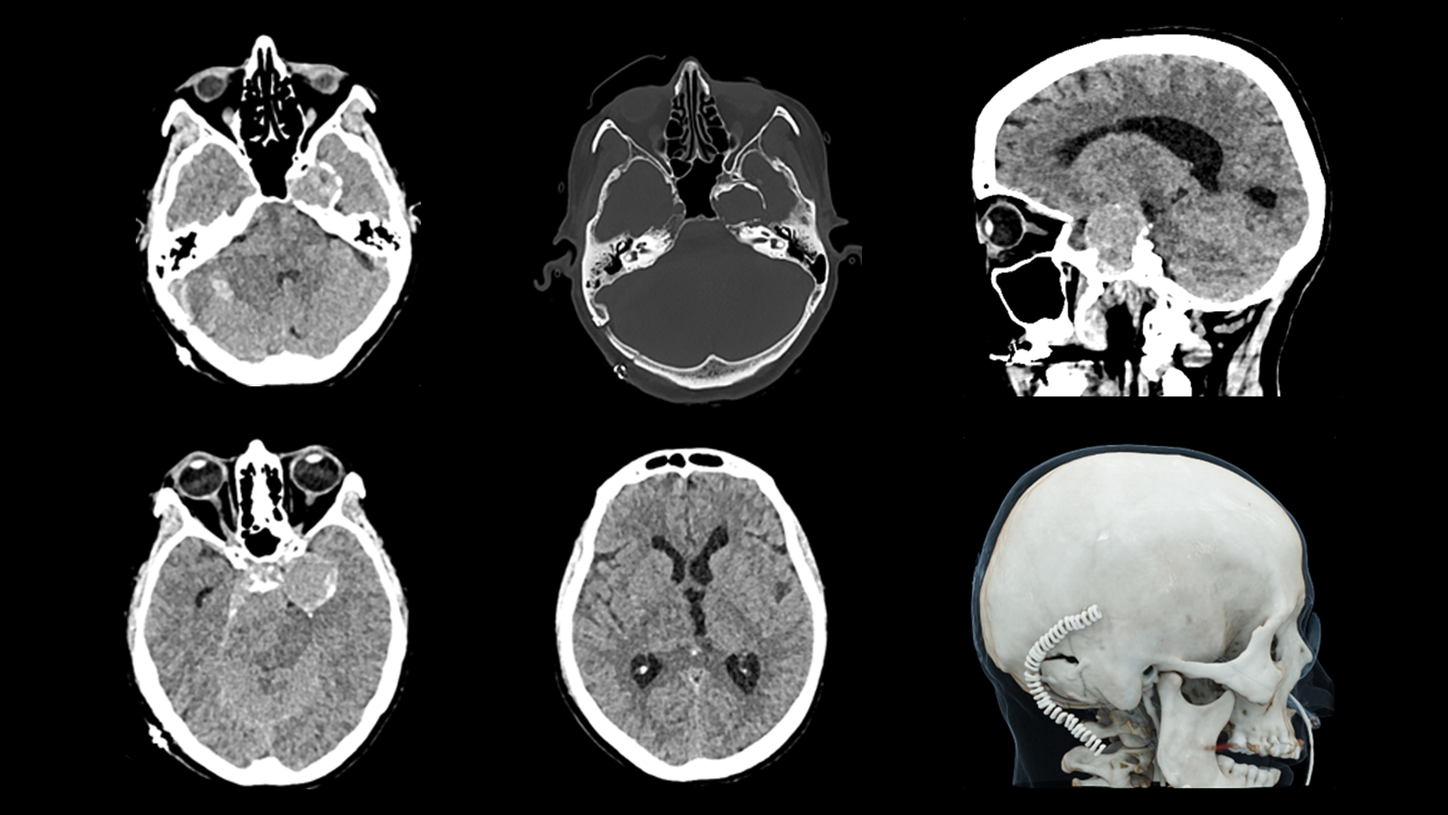

Whether portable in the Intensive Care Unit, or mobile in the ambulance as a Mobile Stroke Unit, SOMATOM On.site is designed to bring critical care imaging to your patients. With the first-of-its-kind telescopic gantry design, integrated positioning accessories, and proven SOMATOM technologies, you can achieve fast and reliable CT head imaging.

Proven SOMATOM technologies such as Stellar detector, iMAR, and ADMIRE® provide high image quality, enabling faster clinical decisions for critical care patients.

Evidence

iMAR